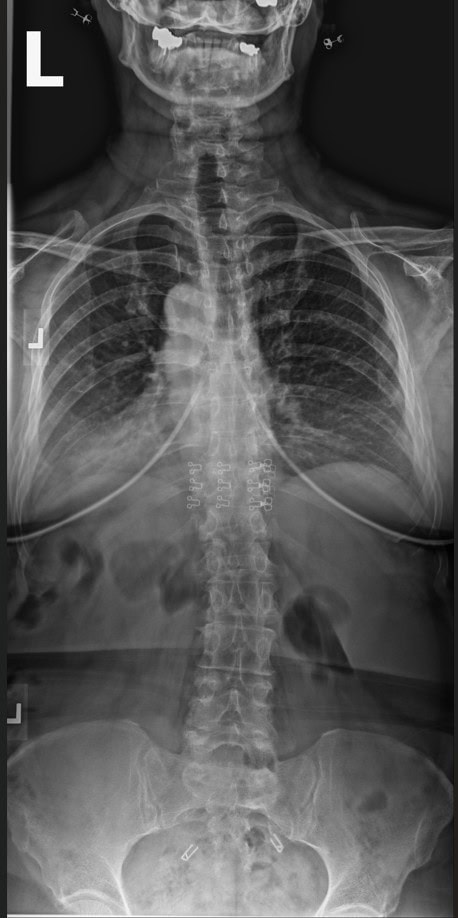

Post Scan